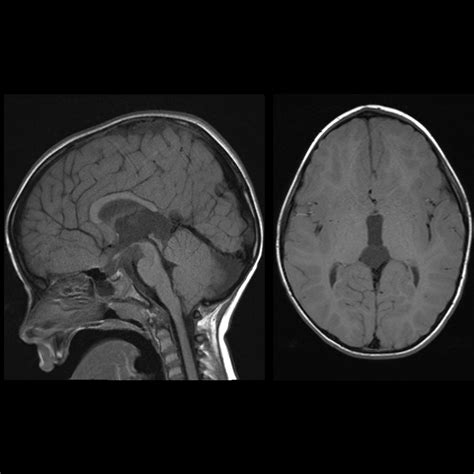

Diagnosing abnormalities in the Cavum Veli Interpositi typically involves the use of advanced imaging techniques. Magnetic Resonance Imaging (MRI) is the most commonly used method for visualizing the Cavum Veli Interpositi and other structures within the brain. MRI provides high-resolution images that allow clinicians to assess the size, shape, and position of the Cavum Veli Interpositi, as well as any potential abnormalities.

Other imaging techniques, such as Computed Tomography (CT) scans and Positron Emission Tomography (PET) scans, may also be used to evaluate the Cavum Veli Interpositi and its surrounding structures. These techniques provide different types of information, such as structural details and metabolic activity, which can be useful in diagnosing and monitoring neurological and psychiatric conditions.

• cavum veli interpositi mri